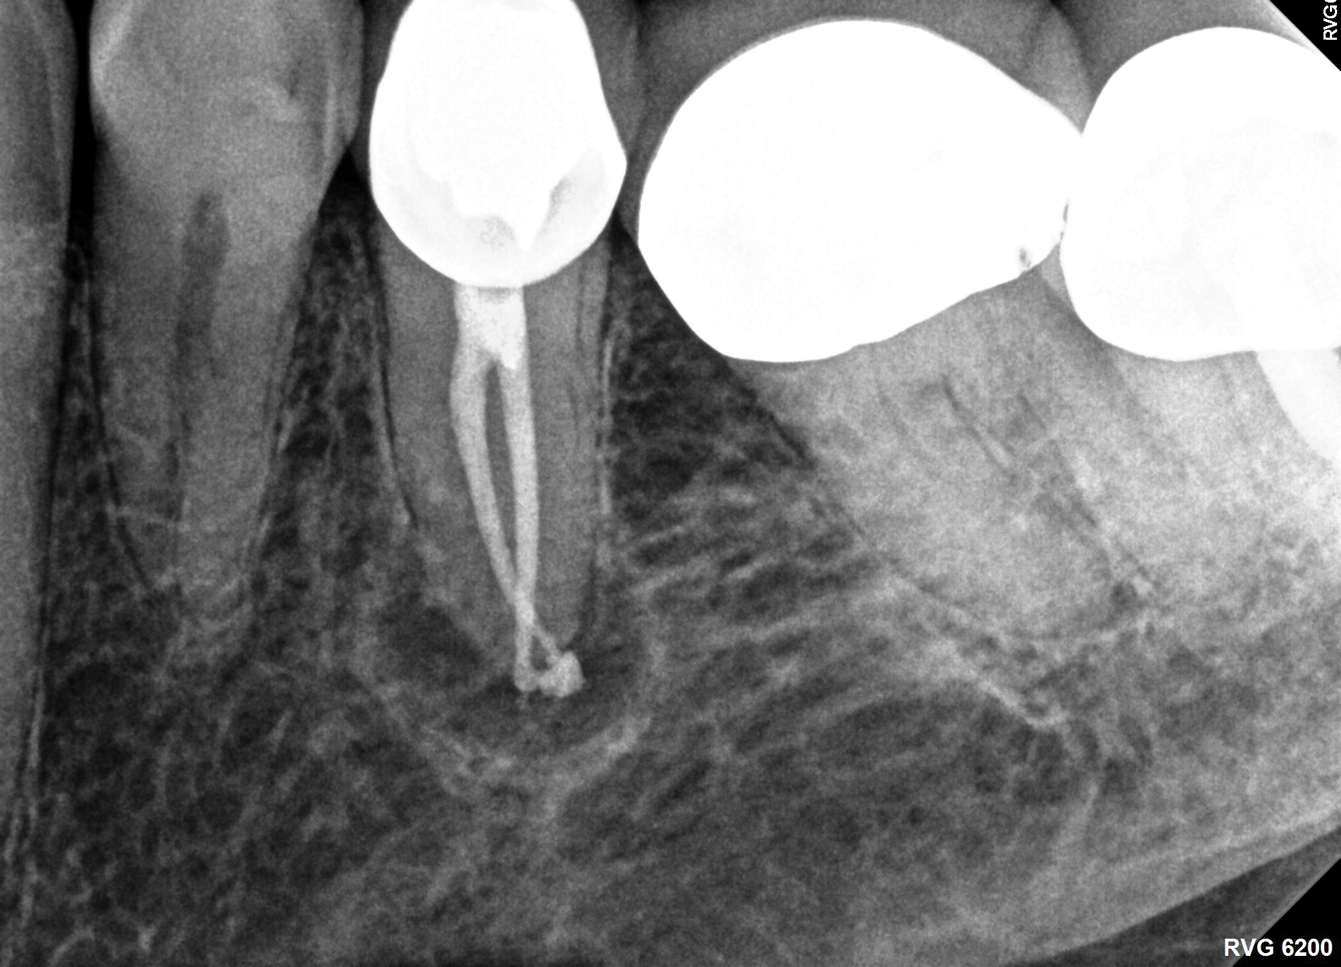

Fig 1. NSRCT can have high success, even with risk factors like periapical pathology associated, as depicted in this case presentation. Fig 1: Preoperative periapical radiograph showing AP. Fig 2: Preoperative CBCT. Fig 3: Immediate postoperative periapical radiograph. Fig 4: Three-month follow-up CBCT showing reduction of periapical radiolucency. Fig 5: One-year follow-up periapical radiograph showing resolution of periapical radiolucency.

Fig 1 through Fig 5. NSRCT can have high success, even with risk factors like periapical pathology associated, as depicted in this case presentation. Fig 1: Preoperative periapical radiograph showing AP. Fig 2: Preoperative CBCT. Fig 3: Immediate postoperative periapical radiograph. Fig 4: Three-month follow-up CBCT showing reduction of periapical radiolucency. Fig 5: One-year follow-up periapical radiograph showing resolution of periapical radiolucency.

Just as systemic conditions and patient habits impact outcomes after NSRCT, the local dental environment and dental disease states also impact outcomes (Figure 1 through Figure 5). In the Toronto study evaluating 4- to 6-year outcomes following NSRCT, the presence of a periapical radiolucency emerged as a key prognostic factor, substantially reducing the success rate by a factor of four.12 Single-rooted teeth experienced better outcomes compared to multirooted teeth in the presence of periapical lesions.1 Teeth diagnosed preoperatively with irreversible pulpitis or necrosis, in the absence of AP, showed a more favorable prognosis compared to those with preoperative AP.2